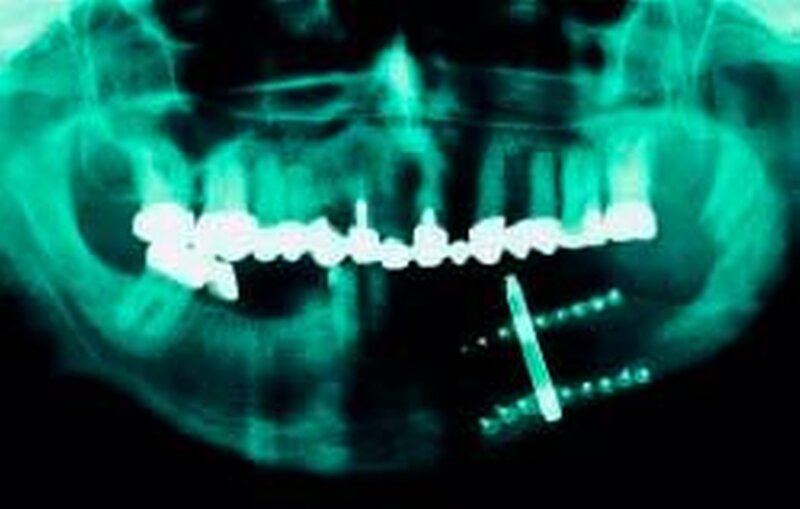

Über die erfolgreiche einzeitige implantatstabilisierte Onlay-Osteoplastik bei Alveolarkammatrophie mit autogenen corticospongiösen Beckenkammtransplantaten berichteten Dr. Dr. Wolfgang Schmüdderich et al., Düsseldorf, die anhand ihrer Untersuchung zeigen konnten, dass neben der weitgehenden Wiederherstellung der Bisslage bei vergleichsweise geringer Komplikationsrate die einzeitige Onlay-Osteoplastik zu einer deutlichen Verbesserung der prothetischen Ausgangssituation mit günstigen Lageverhältnissen zwischen Implantat und Suprastruktur führt. Dass auch die Anwendung von Kalvariaknochen mit simultaner Augmentation und Implantation eine erfolgreiche Methode zur Rehabilitation des atrophen Unterkiefers darstellt, belegte die Untersuchung von Dr. Dr. Ehrenhard Reuter et al., Bremerhaven. Bei keinem Patienten kam es zum Transplantatverlust oder zu einer klinisch relevanten knöchernen Resorption. Die Entnahmemorbidität nach Knochenentnahme am Beckenkamm wurde von Dr. Dr. Manfred Suhr et al., Hamburg, untersucht. Die Knochenentnahme am Beckenkamm bietet neben der geringen Entnahmemorbidität immer die Möglichkeit, Knochen in ausreichender Menge zu gewinnen. Die geringe Entnahmemorbidität am Beckenknochen ist teilweise durch regenerative Prozesse zu erklären, die Prof. Dr. Dr. Claus Udo Fritzemeyer et al., Düsseldorf, vorstellten. Ihre Nachuntersuchung über 20 Jahre zeigte unterschiedliche regenerative Varianten nach Transplantatentnahme, wobei in über 50 Prozent ein knöcherner Restdefekt ohne Durchbauung blieb, welcher insbesondere bei älteren Menschen auftrat. Weiterhin kam es zur Verkleinerung des Entnahmedefektes mit amorpher Knochenproliferation (22 Prozent der Patienten), und nur in 25 Prozent der Fälle fand sich eine fast vollständige und weitgehende Auffüllung der Knochenwunde. Die häufigste zusätzliche Reparationsvariante bestand in einer Spornbildung am Defektrand, die bei 58 Prozent aller Patienten auftrat.